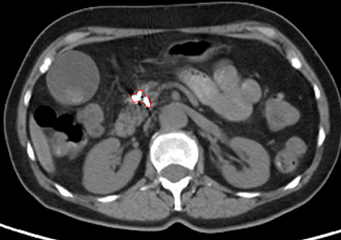

比瑞特的CT图示治疗前胰腺头体部巨大肿瘤,活捡腺癌;

治疗后10个月复查CT,显示病变显著缩小,PET上无活性,提示肿瘤坏死